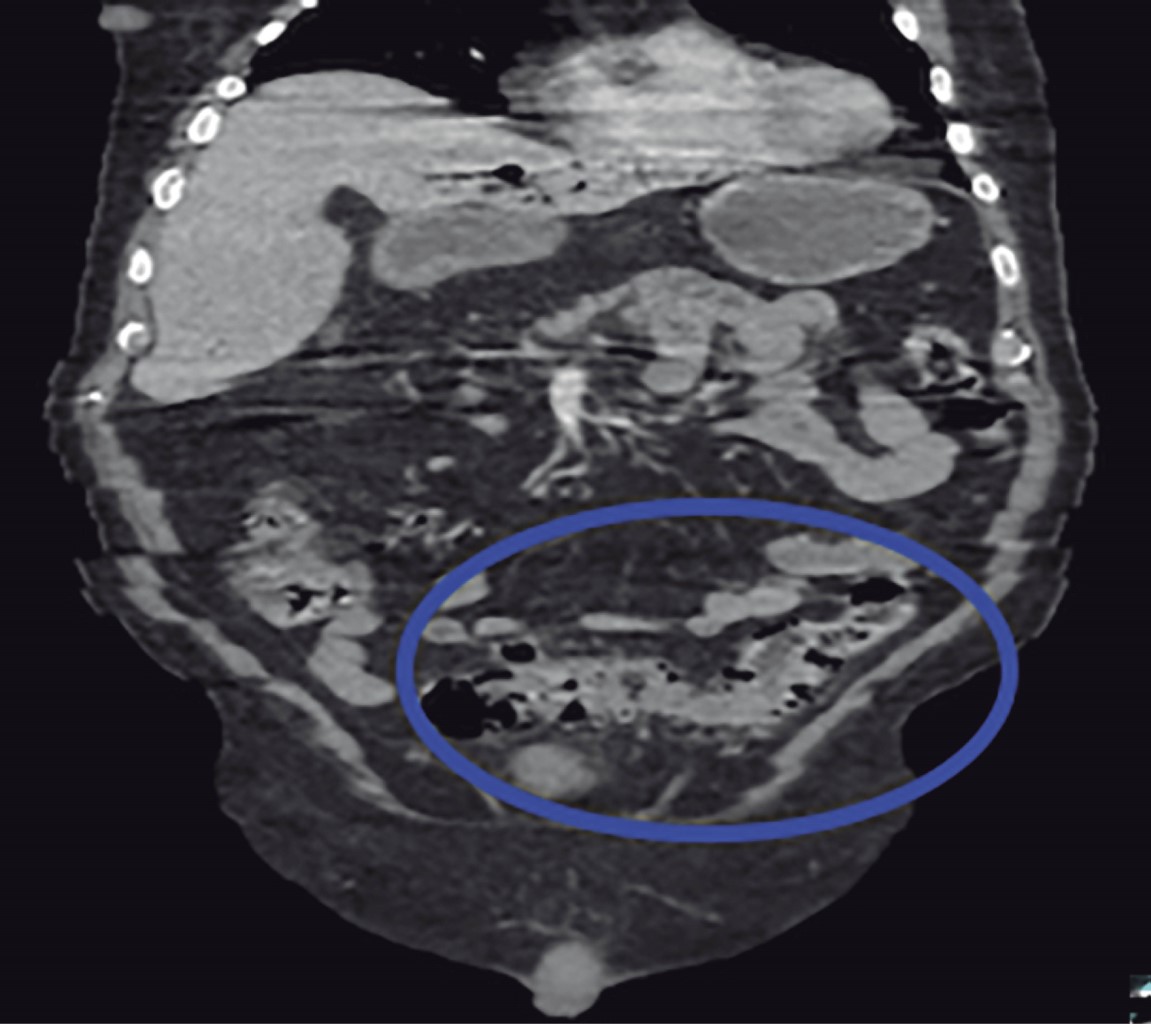

Masculino de 77 años con antecedentes de diabetes mellitus 2 e hipertensión arterial sistémica de larga evolución, antecedentes quirúrgicos de colecistectomía laparoscópica hace seis años y cateterismo cardiaco por cardiopatía isquémica crónica. Inicia su padecimiento actual 10 días previos a su ingreso con cuadro de dolor abdominal difuso en cuadrantes inferiores, así como ataque al estado general acompañado de astenia e hiporexia. Fue manejado por facultativo externo con antibioticoterapia. A su llegada al Servicio de Urgencias se presenta con taquicardia y tendencia a la hipotensión acompañado de alteración del estado de alerta. A la exploración física se palpa plastrón inflamatorio en cuadrante inferior izquierdo que despierta dolor a la manipulación del mismo, sin embargo, no hay datos de irritación peritoneal, sus laboratoriales con leucocitos 13,400 mm3, neutrofilia 92.9% y lactato de 3.9 mmol/l. Se solicita tomografía abdominopélvica contrastada en donde se muestra trombosis de la vena porta (Figura 1), neumatosis portal (Figura 2) y enfermedad diverticular (Figura 3), por los hallazgos anteriores se da manejo inicial con soluciones intravenosas y antibioticoterapia empírica de amplio espectro con piperacilina-tazobactam 4.5 g IV cada 8 horas, posterior al manejo estabilizador se realiza laparotomía exploradora, en donde se realiza sigmoidectomía y colostomía terminal debido a los hallazgos de perforación diverticular (Figuras 4 y 5) y plastrón inflamatorio purulento en el mesosigmoides con especial distribución en el trayecto de la vena mesentérica inferior, se toma cultivo y se maneja el posoperatorio en terapia intensiva, se deja antibioticoterapia dirigida a E. coli. Se calcula nutrición parenteral total y se inicia terapia anticoagulante con enoxaparina 60 mg subcutáneos (SC) cada 12 horas. El paciente cursó con evolución clínica favorable gracias al manejo multidisciplinario que se brindó. Egresó a la semana del procedimiento quirúrgico sin complicación alguna, se cita a consulta externa una semana después de su egreso tolerando vía oral con estoma funcional y con la herida afrontada. El reporte de histopatología reveló enfermedad diverticular complicada.

Figura 3